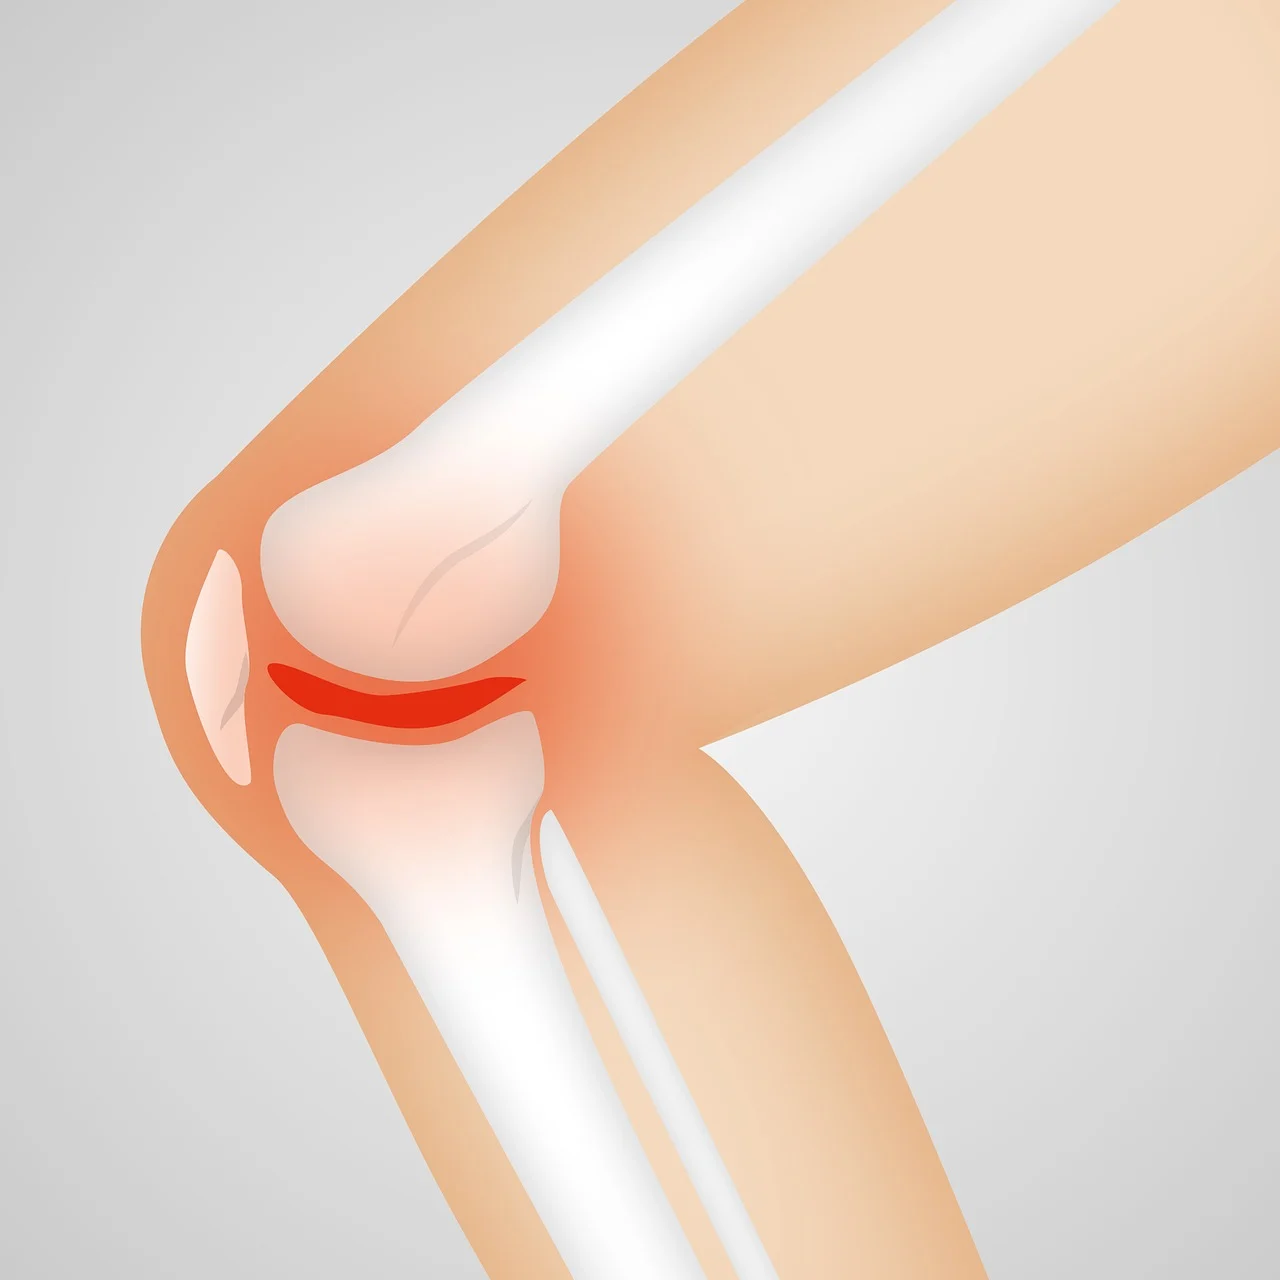

콘드로이친은 관절 사이에서 염증을 줄이고, 마찰을 줄여주는 윤활 작용을 해줍니다. 이 두 가지 기능 덕분에 관절 통증과 불편함이 줄어드는 것이죠.